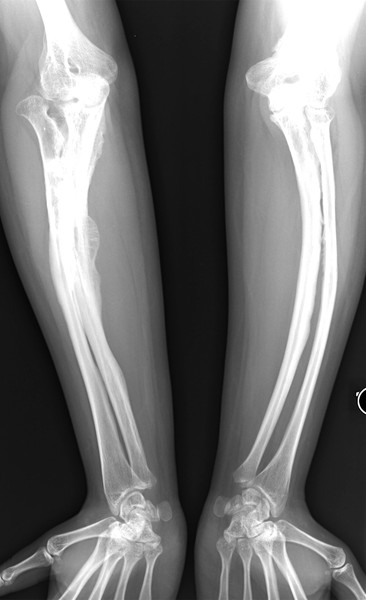

成骨不全症係因基因突變,導致形成骨骼的主成分「膠原纖維」異常,因而造成骨骼脆弱易折、耐受力差,每2至3萬人中就有1人罹患該罕見疾病。部分患者在幼年學步時大腿骨等長骨容易骨折,脊椎易發生壓迫性骨折造成側彎。根據英國「脆骨病協會」統計,玻璃娃娃長至18歲時,將可能發生2至3百次骨折。